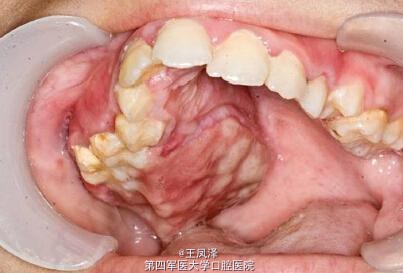

患者女,9 岁,发现右侧上颌骨无痛性肿块 3 个月余。查体见右侧上颌骨明显肿胀,质硬,不可活动,触之无疼痛感,约 3 cm× 2 cm 大小。肿块自右侧颊部向右侧腭部膨隆,右侧上颌牙齿移位,I 度松动。余未见明显异常